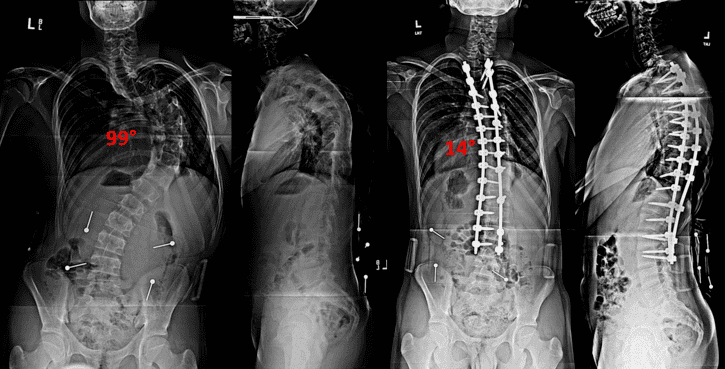

Pokud je boční prohnutí 20 – 25 stupňů, lékaři předepisují podpěru, nebo korzet. Pokud prohnutí postupuje na víc než 45 stupňů, je pacientovi doporučena operace.

Zvýšeným tlakem dál trpí meziobratlové disky (ploténky) a nervy kolem páteře. Člověk začne mít také problémy s dýcháním, což je u pokročilé skoliózy častý jev. Pacienti, kteří podstoupí operaci (což je velmi nepřirozená až drastická procedura, zahrnující kovové tyče, háky, dráty a šrouby, kromě jiného, které násilně nutí páteř do vzpřímené polohy), ztrácí až 60% flexibility páteře a po zbytek života trpí chronickou bolestí, což způsobí znehybněná páteř, kovy a nepřirozené předměty v páteři, které vedou následně k degeneraci meziobratlových plotének (disků) a osteoathritis.

Podle studie (publikované v medicínském časopise Spinal), která proběhla v roce 2008, bylo posuzováno 32 pacientů po operaci páteře (spinal fusion surgery) a u 75% z nich byla zjištěna degenerace sacroiliakálního spojení (Si skloubení) už velmi brzy po operaci.

Ve stejném roce proběhla další velmi rozsáhlá studie, podle které bylo zjištěno, že nárůst rozsáhlých komplikací po operacích je alarmující, až 89%.

I když jsou obratle chirurgickým zákrokem drženy na místě pomocí kovových prvků, navyklé (mimovolní) kontrakce svalů kolem páteře způsobují mikropohyby, které brání neustálému přirozenému růstu kostí (protože kost je živá tkáň, osteoblasty a osteoklasty nemohou dělat svoji práci). Nebo jsou kontrakce svalů kolem páteře tak silné, že může dojít ke zlomení kovových prutů, které drží páteř, což způsobí pacientovi nepředstavitelnou bolest a často nutnou potřebu další operace. Většina takových pacientů se proto stává trvale závislými na „lécích“ od bolesti (tady je vhodnější anglický výraz DRUGS) a později na antidepresivech, což jsou psychofarmaka, návykové látky s velmi devastačními vedlejšími účinky. A pokud je takovými pacientem dítě nebo dospívající jedinec, jaký život má před sebou?

Pro vysoké riziko komplikací po operacích a jen velmi málo důkazů pro efektivitu operace došli lékaři v roce 2008 k závěru, že operace by měly být nadále prováděny pouze v nezbytně nutných případech, pro zpomalení progrese tvorby bočního oblouku páteře, ale tento druh operace není ideální pro dlouhodobé řešení.